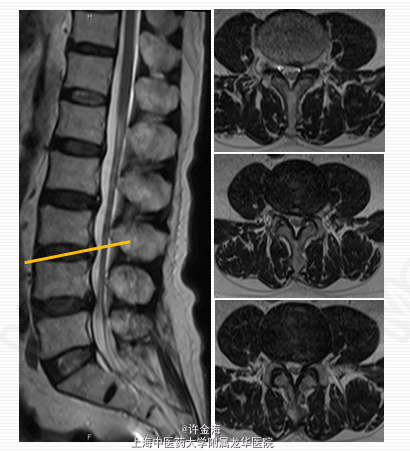

主诉:腰痛伴右下肢放射痛1天 病史:患者腰部疼痛三月,1天前腰部扭伤后出现右下肢放射痛

静脉:20%甘露醇250mlX3d 凯纷5ml+生理盐水250X7d 红花20ml+生理盐水250X7d 艾灸:督脉经、膀胱经 电针:足阳明胃经(伏兔、梁丘、足三里、条口) 足太阳膀胱经(肾腧、大肠腧、秩边、委中、承山) 中药内服:

2周后评分:腰VAS2分;腿VAS2分;JOA22分 出院后续治疗:服用中药3月;电针、艾灸每周1次 5月后随访: 复查MRI:游离椎间盘消失 评分:腰VAS0分;腿VAS1分;JOA26分 体检:腰部活动正常,双下肢直腿抬高试验>70°,肌力V级,浅感觉正常,膝踝反射(++),病理征(-)。